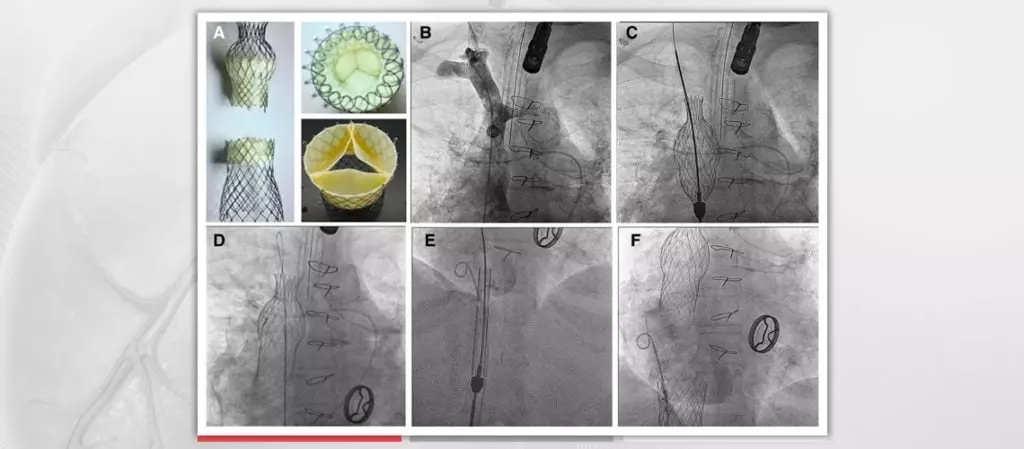

Transcatheter caval valve implantation is under evaluation as a treatment option for inoperable patients with severe tricuspid regurgitation (TR). The procedure involves the catheter-based implantation of bioprosthetic valves in the inferior vena cava and superior vena cava to treat symptoms associated with TR. This study is the first to evaluate the feasibility, safety, and efficacy of this interventional concept.